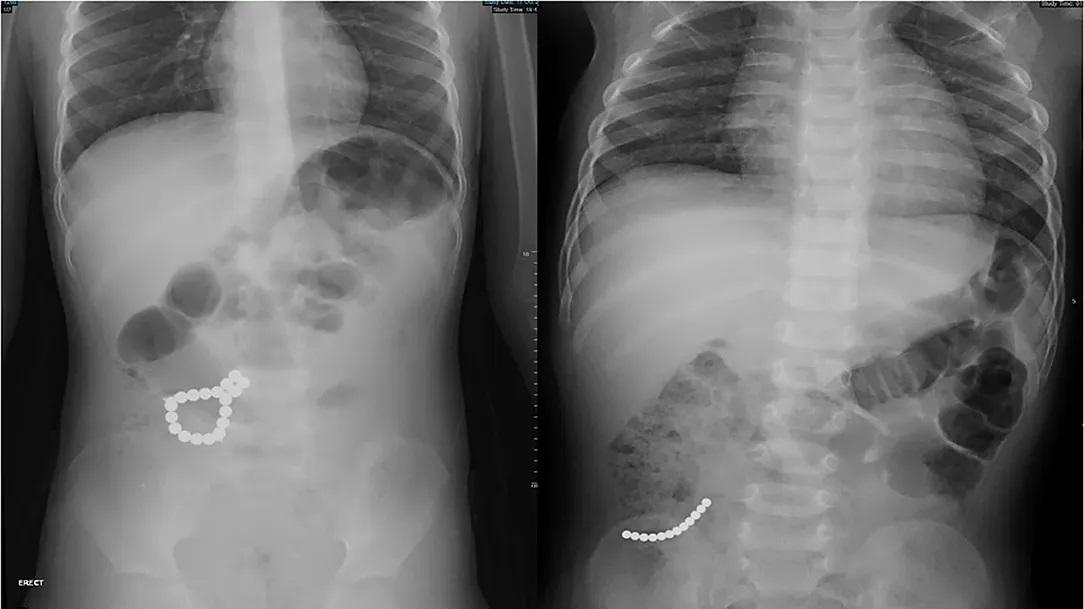

醫生為該名男孩照X光及電腦掃描,結果發現多件異物,於是首先以手術取出已嵌入胃壁的3粒異物,並確認為磁石。然後醫生再在大腸位置發現3粒磁石,且已令腸道出現腐爛。進一步檢查再發現另外有15粒磁石分布在大腸及小腸不同位置,大部分都需要以手術移除,而且部分腸壁已有破孔。

X光下發現體內多件異物。